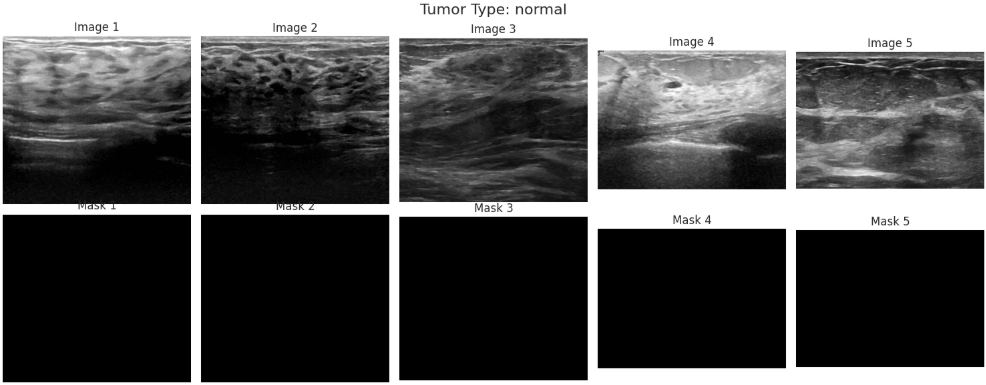

在了解数据集的类别分布之后,还需要进一步观察具体图像样本及其对应的标注信息。乳腺超声数据集中不仅包含原始图像,还提供了对应的病灶掩膜(mask),这些掩膜标注能够指示病灶区域的位置,对于后续模型学习病变区域特征具有重要意义。因此,通过随机抽取不同类别样本并同时展示原始图像与对应掩膜,可以直观了解数据质量以及标注的准确性,从而为后续模型设计和训练提供更加清晰的参考。

for tumor in tumor_types:

fig.suptitle(f"Tumor Type: {tumor}", fontsize=16)